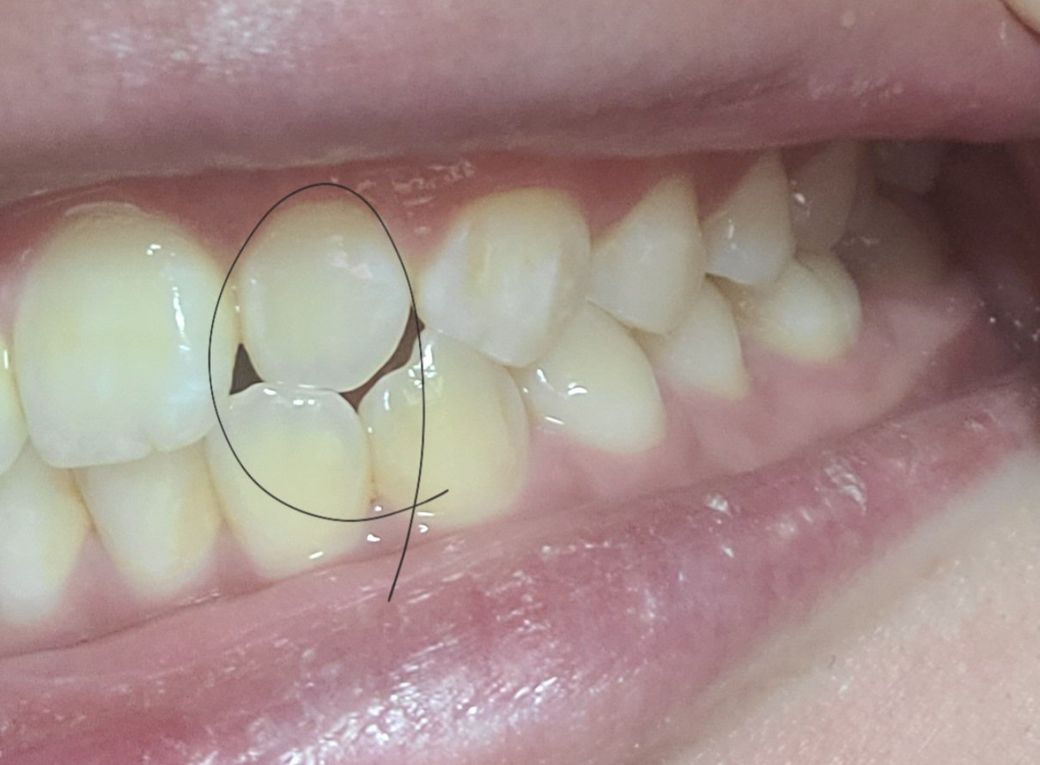

제일 위 첫번째 사진에서 윗니 1개(측절치)가 아랫니(측절치) 보다 안쪽으로 들어가 있어 정상 치아 교합이 아닙니다

왼쪽이 제1소구치쪽부터 교합이 아주 이상적인 교합은 아닙니다. 또한, 오른쪽 2번째 치아는 원래 위 치아가 아래치아를 덮어야하는데, 그렇지 않고 치아끼리 바로 닿습니다. 이 경우 치아에 무리가 갈 수 있습니다.

치아는 상악치아가 하악 치아보다 앞으로 살짝 나와있기 때문에 치아를 덮으면서 빈공간이 없어보이게 됩니다.

하지만 사진과 같이 오른쪽 2번째 윗니와 아랫니가 절단교합이 되어 있으면 치아가 다 내려오지 않아서 공간이 보일수 있어요.